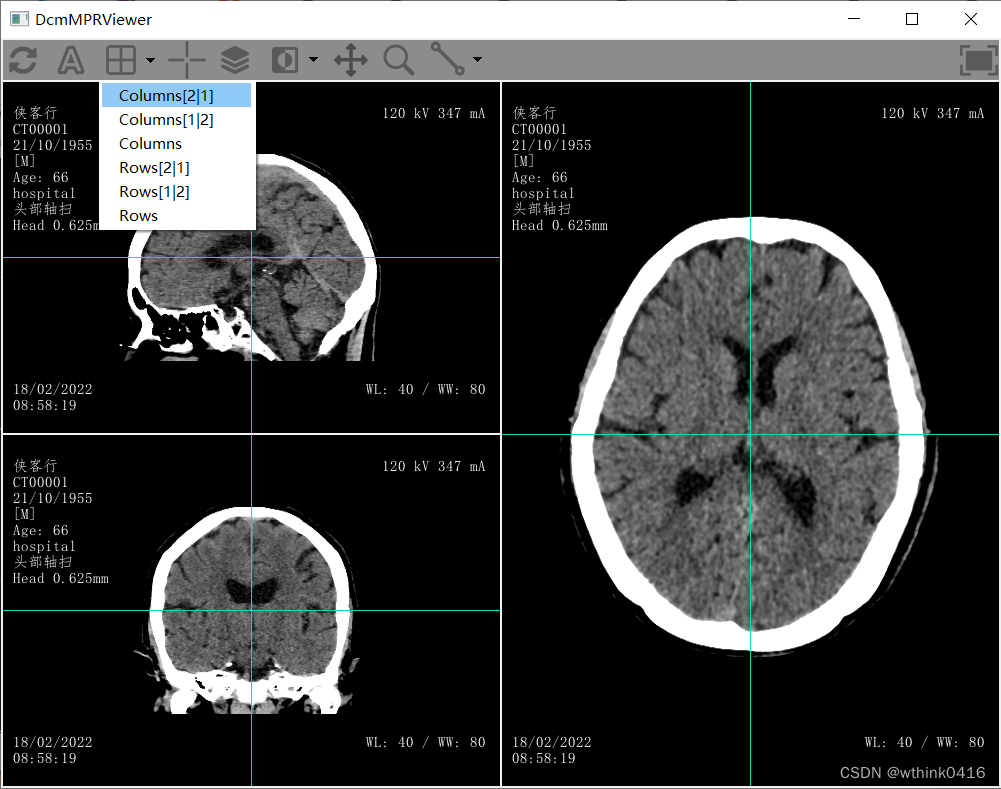

18、点击![]() 分格图标,可切换布局

分格图标,可切换布局